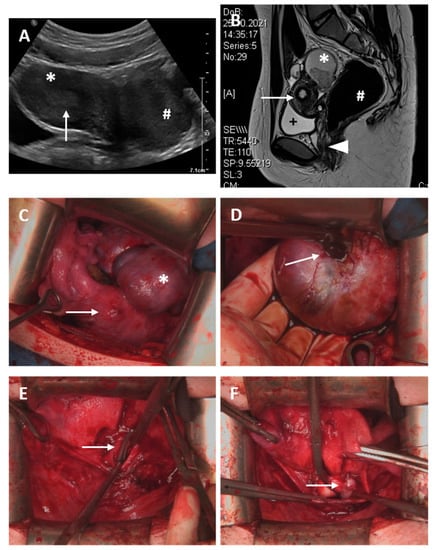

A 13-year-old girl presented with acute abdominal pain; therefore, emergency laparoscopy was performed. In addition to the medical history of multiple malformations such as bilateral double kidneys, skeletal malformations, anal atresia and tetralogy of fallot—for which surgery had been performed previously—laparoscopy showed vaginal and cervical atresia with a considerably enlarged right-sided hemiuterus and a rudimentary left uterine horn (ESHRE/ESGE classification: U4a/C4/V4), as depicted in Figure 2. After transfundal incision, pus was discharged. Then, a neovagina was created using the modified McIndoe procedure, and within the same surgery, a vaginally assisted laparoscopic uterovaginal anastomosis was established and a catheter was placed to contain the anastomosis. Five days later, the catheter was removed, and hysteroscopy and laparoscopy and reconstruction of the cervix were performed. A Fehling tube was inserted into the newly formed cervix, and the patient was instructed to use a vaginal stent at night. One month later, in March 2012, although the Fehling tube was still in the correct position within the uterovaginal anastomosis with no sign of hematometra, the vagina had obliterated completely and had to be reopened. Although a cervical formation had been performed in earlier surgeries, a cervix could not be identified. The Fehling tube was left within the anastomosis, and a vaginal device was placed into the vagina. Two months later, the patient presented for the removal of the vaginal device and Fehling tube. The neovagina was completely epithelialized and showed no sign of adhesions. However, the previously created cervix could now be identified as such. Aside from a small cervical polyp, hysteroscopy showed a normal cervical canal and hemiuterus. Follow-up examinations 1 and 3 months later showed no sign of hematometra, and menstruation occurred regularly. In November 2012, the patient was admitted due to pyometra for antibiotic and surgical treatment. The vagina had obliterated to a length of 2 cm, and the cervix was constricted. After dilation, pus discharged from the uterus. Vaginal reconstruction was performed, and a vaginal phantom was inserted. Follow-up examinations showed no sign of hematometra, and regular menstruation was achieved under oral hormonal contraceptive therapy. In September 2013, the patient was admitted again for therapy of pyometra. Laparoscopy and hysteroscopy showed advanced adhesions, which were cleaved. Follow-up 3 months later showed no sign of hemato- or pyometra, although menstruation was temporarily suppressed by hormonal therapy. The last presentation at our clinic was in 2018; menstruation occurred regularly, sexual intercourse was satisfying with a vaginal length of 7 cm and there was no sign of hemato- or pyometra.

Figure 2.

Case 2. (A) Magnetic resonance imaging from the pelvis; * hematometra (6.5 × 6.1 × 8.6 cm); arrows show vaginal atresia; # bladder. (B) Introitus vagina with vaginal atresia. (C) Laparoscopic view of an enlarged right-sided uterus unicornis (*) and a rudimentary left uteral horn (#). (D) Discharge of pus after transfundal incision (arrows); # left rudimentary uteral horn. (E) Arrow shows intracervical Fehling tube after vaginal and cervical reconstruction. (F) Transabdominal sonography; the uterus is displayed with normal endometrium on the left side; the right side of the picture, the intracervical Fehling tube is indicated by small arrows. (G) Vaginal device (*) with intracervical Fehling tube (arrow). (H) Fehling tube within the uterovaginal anastomosis (arrow), completely epithelialized neovagina (*). (I): Latest hysteroscopy after relief of pyometra and cleavage of adhesions.